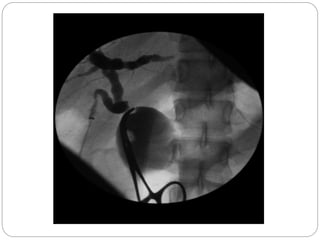

• On ultrasound or CT the biliary tree

dilatation or cyst can be seen.

• 99mTc-HIDA scinitraphy will show

accumulation of tracer within the cyst.

• Percutanous or endoscopic

cholangiography and MRCP are

helpful in preoperative planning.

Fusiform choledochal cyst with a long common channel

and associated stricture at the pancreaticobiliary junction.

Fusiform choledochal cystwith a long common channel and associated stricture at the pancreaticobiliary junction.